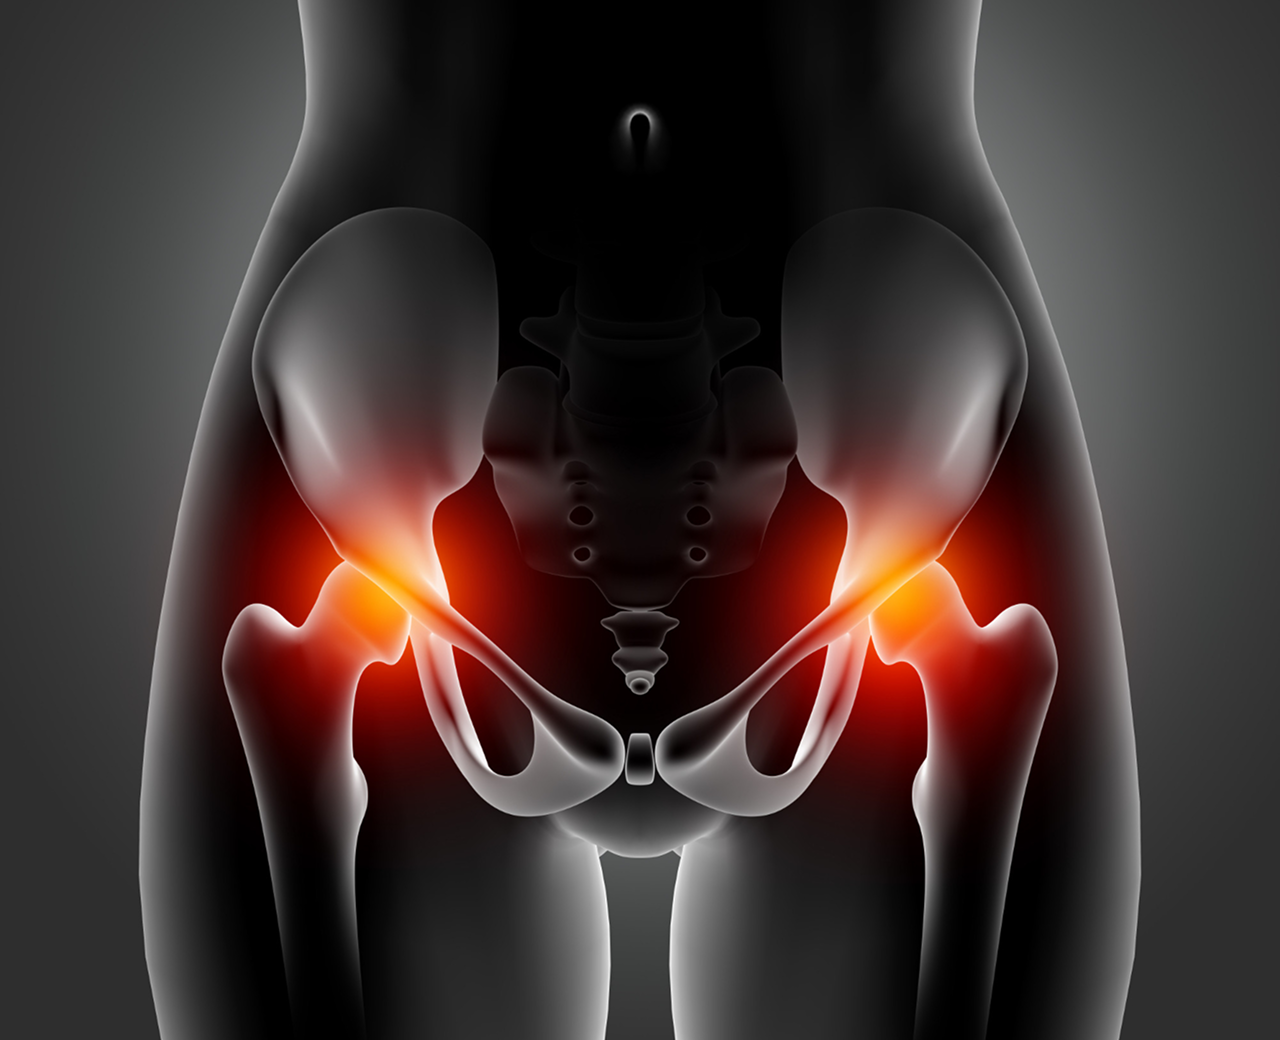

Hip pain

Hip Pain Treatment

in Duluth, GA

As we age, our body's ability to regenerate declines, making us more vulnerable to degenerative conditions such as hip pain caused by osteoarthritis.

If left untreated, these conditions can significantly impact your daily life, potentially leading to joint replacement surgery, which involves painful procedures, anesthesia, and a long recovery process.

Hip replacement surgery also comes with risks, including a 1% mortality rate, complications like infections, blood clots, and the possibility of requiring multiple surgeries.